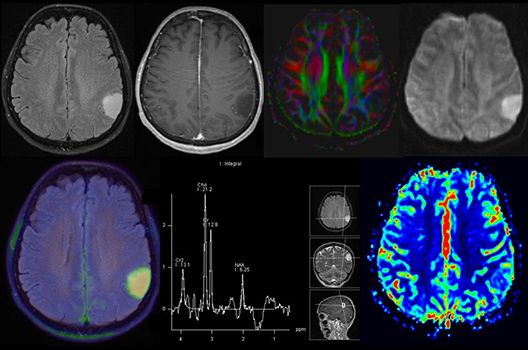

- MR-Diffusionstensorbildgebung (Faserbahndarstellung/fiber tracking)

Die Schwerpunkte in der MR-Forschung liegen in der multiparametrischen und funktionellen Bildgebung bei onkologischen und anderen, neuroradiologischen Fragestellungen und umfassen die Anwendung modernster MR-Verfahren sowie die Untersuchung an Hochfeld-Geräten.

Die Magnetresonanztomographie (MRT) ist ein Verfahren, bei dem durch magnetische Kräfte Bilder des Körperinneren angefertigt werden. In der Neuroradiologie können manchmal kleinste Veränderungen schwere Folgen haben; daher forschen wir an der Entwicklung hochauflösender MRT-Sequenzen, mit denen diese Prozesse und auch einzelne Nervenfaserbahnen sichtbar gemacht werden können. Darüber hinaus sind bei vielen Erkrankungen des Gehirns die Blutgefäße betroffen. Daher arbeiten wir an der Neu- und Weiterentwicklung von MRT-Sequenzen zur Darstellung der Blutgefäße und zur Blutflussanalyse (sog. „Angio-MRT“). Einen besonderen Forschungsschwerpunkt unserer Klinik stellen die MR-Protonenspektroskopie und die funktionelle MRT dar, mit denen die Analyse einzelner chemischer Substanzen im Hirngewebe oder die Darstellung ausgewählter Hirnfunktionen möglich ist.

Die bildgebende Diagnostik und Verlaufsbeurteilung von Tumoren des Nervensystems ist einer der klinischen und Forschungsschwerpunkte unserer Abteilung. Eine besondere Bedeutung kommt der Hybrid-Bildgebung zu. Das Universitätsklinikum verfügt über einen integrierten Ganzkörper-PET/MRT-Scanner, der die Vorteile der MRT-Bildgebung und der Positronenemissionstherapie (PET) vereinigt. Aufgrund der langjährigen klinischen Arbeit und Forschungstätigkeit mit diesem Gerät hat die Neuroradiologie Tübingen maßgeblich zur Etablierung dieses Verfahrens beigetragen. Auch weiterhin forschen wir intensiv an neuen Methoden zur frühen Einordnung von Tumoren und insbesondere Tumorrezidiven, die mit anderen Methoden häufig nicht erfasst werden können.